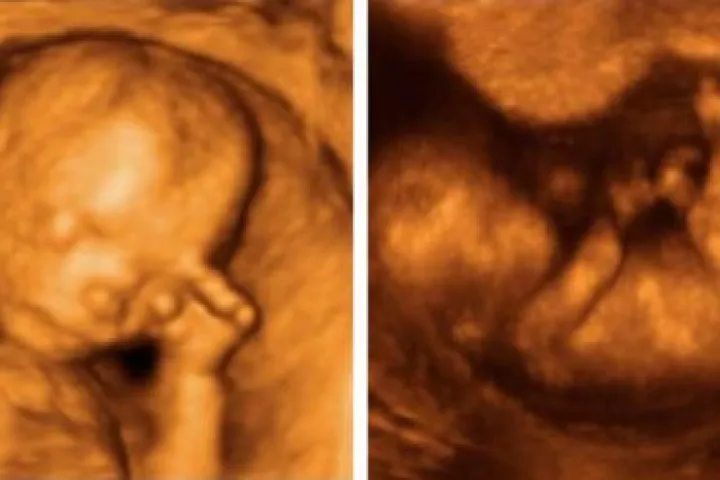

Um grupo de pesquisadores das universidades Durham e Lancaster, no Reino Unido, revelou que as crianças no ventre podem sentir o estresse de suas mães, e inclusive podem expressar este mal-estar fisicamente, mexendo a sua mão esquerda para o rosto.

Para realizar a pesquisa, os cientistas britânicos utilizaram ecografias em 4D, com as que observaram 15 bebês e gravaram 342 ocasiões nas quais se tocaram o rosto.

As imagens foram captadas em quatro etapas diferentes da gravidez, entre a 24ª e 36ª semanas.